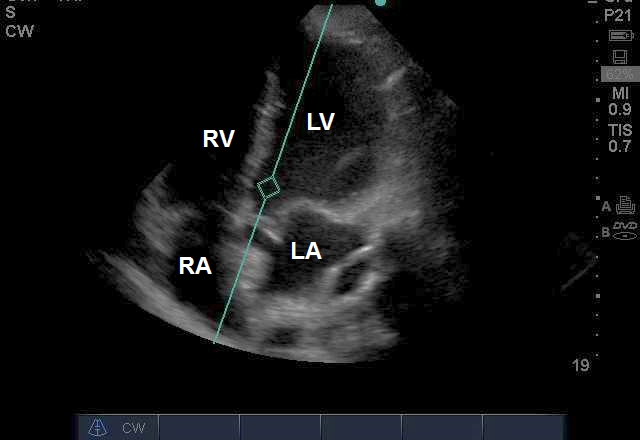

Case 7-4. Subcostal Long-axis View

Video 7-4A. The right ventricle (RV) and right atrium (RA) are enlarged. The RV free wall is thickened, suggesting that the RV has been under chronic load. This would require M-mode or caliper based measurement, if there was need for quantitative purposes. The intra-atrial septum is bowed into the left atrium, suggesting elevation of RA pressure. This is supported by the presence of a dilated coronary sinus. The left ventricular function is normal; although at a qualitative level, it appears to be compressed by the RV.

Video 7-4B. Color Doppler grid positioned over the intra-atrial septum, with the purpose of checking for a patent foramen ovale in this patient with severe hypoxemic respiratory failure. There was no color Doppler evidence of right to left shunt. This was confirmed with agitated saline contrast injection. At times, the LV seems to have end-systolic effacement. This is an artifact of respiratory translational artifact that is a common feature of critical care echocardiography performed on the acutely dyspneic patient.